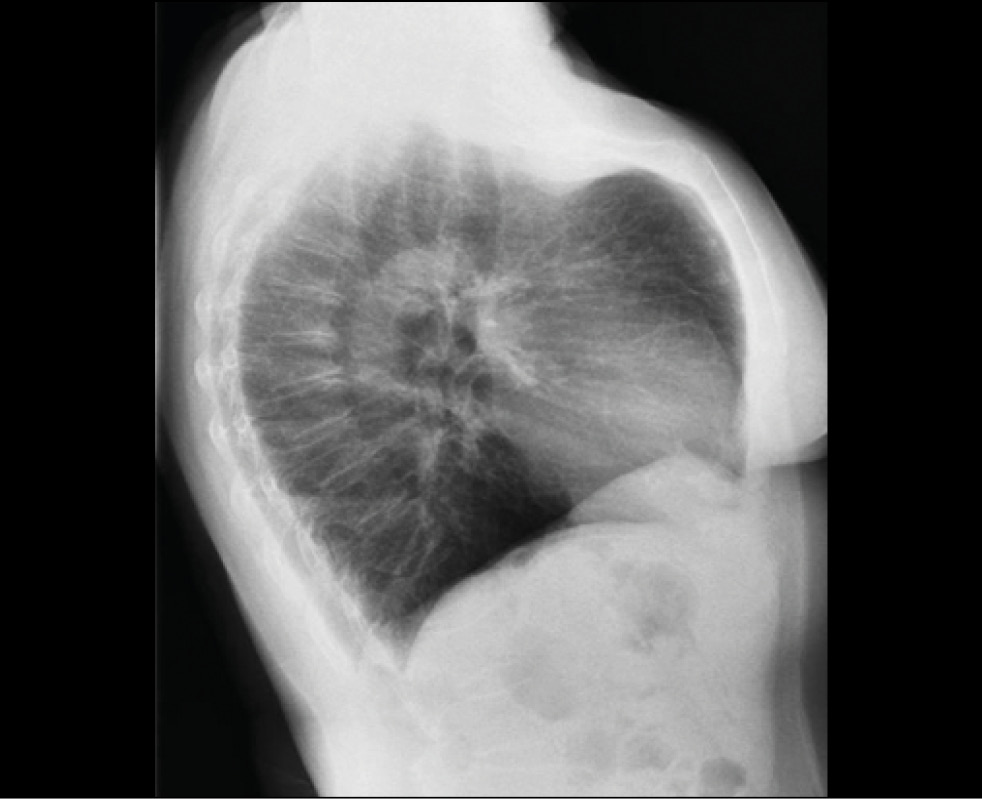

Fig 3. Lateral plain radiograph appearance of a type 2 pectus carinatum.